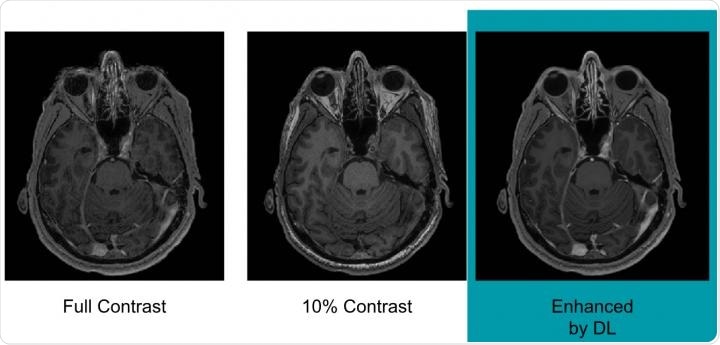

Pre-contrast scans carried out before any contrast had been administered were referred to as zero-dose scans; those that used 10% of the standard gadolinium dose were referred to as low-dose scans and those that used 100% of the standard dose were referred to as full-dose scans.

Example of full-dose, 10 percent low-dose and algorithm-enhanced low-dose. Credit: Radiological Society of North America.Gong says the results indicate the method’s potential for significantly reducing the gadolinium dose, without compromising diagnostic quality: